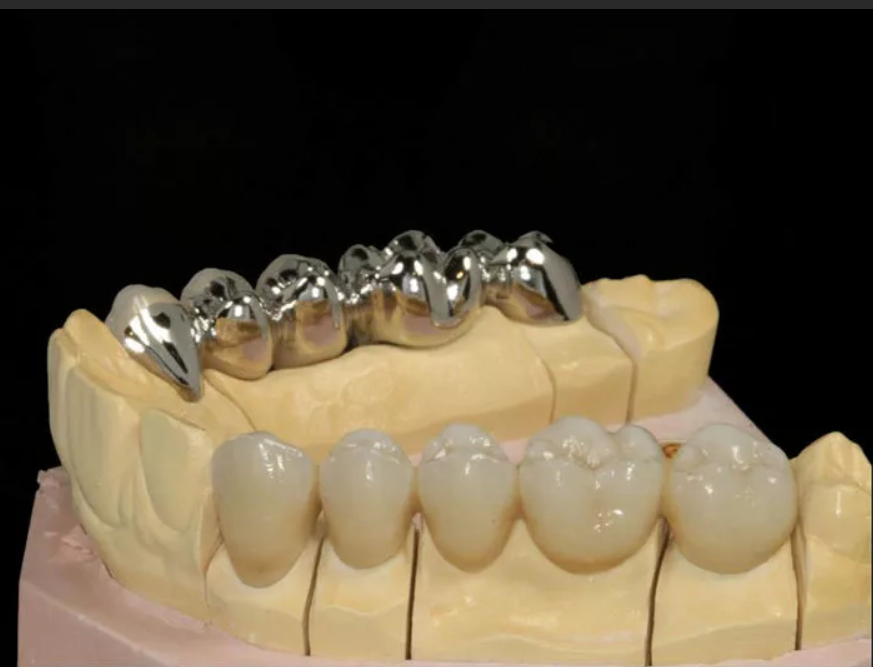

Металлические коронки на зубах

В стоматологии часто применяют металлические коронки при разрушении зубов. Если коронка выполняется только из металла, то на нее напыляется медь, При металлокерамических коронках напыление производится из керамики. При постановке таких протезов будет возникать вопрос, можно ли делать МРТ с металлическими коронками на зубах.

Выполнять магнито-резонансную томографию с металлическими коронками нельзя, а с металлокерамическими – можно.

Крепежные элементы для коронок выполняются из следующих материалов:

- сталь;

- никель;

- кобальт;

- железо.

Они оказывают влияние на магнитное поле томографа. Нагревание этих материалов незначительное. Оно не ощущается человеком, не оказывает отрицательного воздействия на окружающие ткани. Но эти крепежи будут искажать изображения на снимках. Сплавы из золота не нагреваются, но тоже изменяют компьютерное изображение.